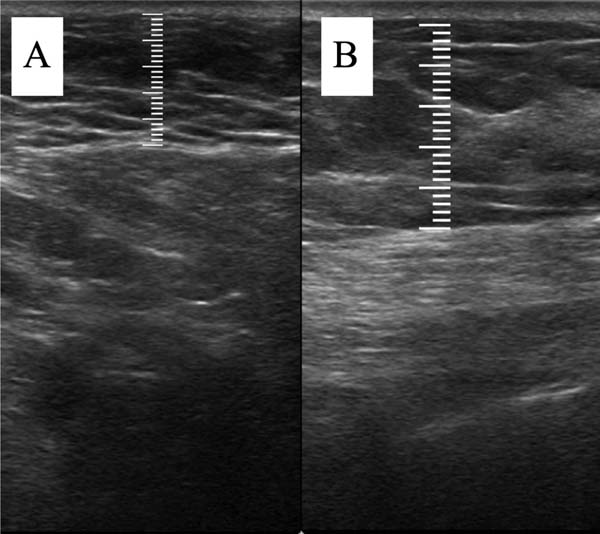

Dentro do quadrante mamário com queixa de baixa volu-mização, é estabelecido um ponto fixo para mensuração da espessura subcutânea durante todo o acompanhamento. Esse ponto é definido como a região central do quadrante e a menor distância desse ponto até a clavícula e até a divisão do quadrante mamário mais próxima é registrada para que o ponto seja reprodutível nas próximas mensurações. ►Fig. 1.

A mensuração da espessura do tecido subcutâneo é realizada de forma vertical, do ponto mais alto (logo na transição da epiderme) ao ponto mais baixo (na transição com o tecido muscular) da espessura de tecido subcutâneo. Essa medida é de fácil reprodutibilidade para quem possui aptidões básicas em ultrassonografia. ►Fig. 2. A medida da espessura de tecido subcutaneo na mama lipoenxertada foi realizada no pré- e pós-operatório imediato da lipoenxertia, e após 15,30, 90 e 180 dias. As medidas foram feitas atraves da ultrassonografia, em milimetros, medindo a distancia vertical do ponto mais superior (proximo à epiderme) ao mais inferior (proximo à musculatura adjacente) do tecido subcuta neo no ponto previamente definido. Foi utilizado equipamento de ultrassom modelo GE, LOGIQP6 (GE Healthcare) com uso de sonda linear de 11L com faixa de frequencia de 12 a 6 MHz, operado por cirurgião com pós graduação lato sensu em ultrassonografia geral. ►Fig. 3.